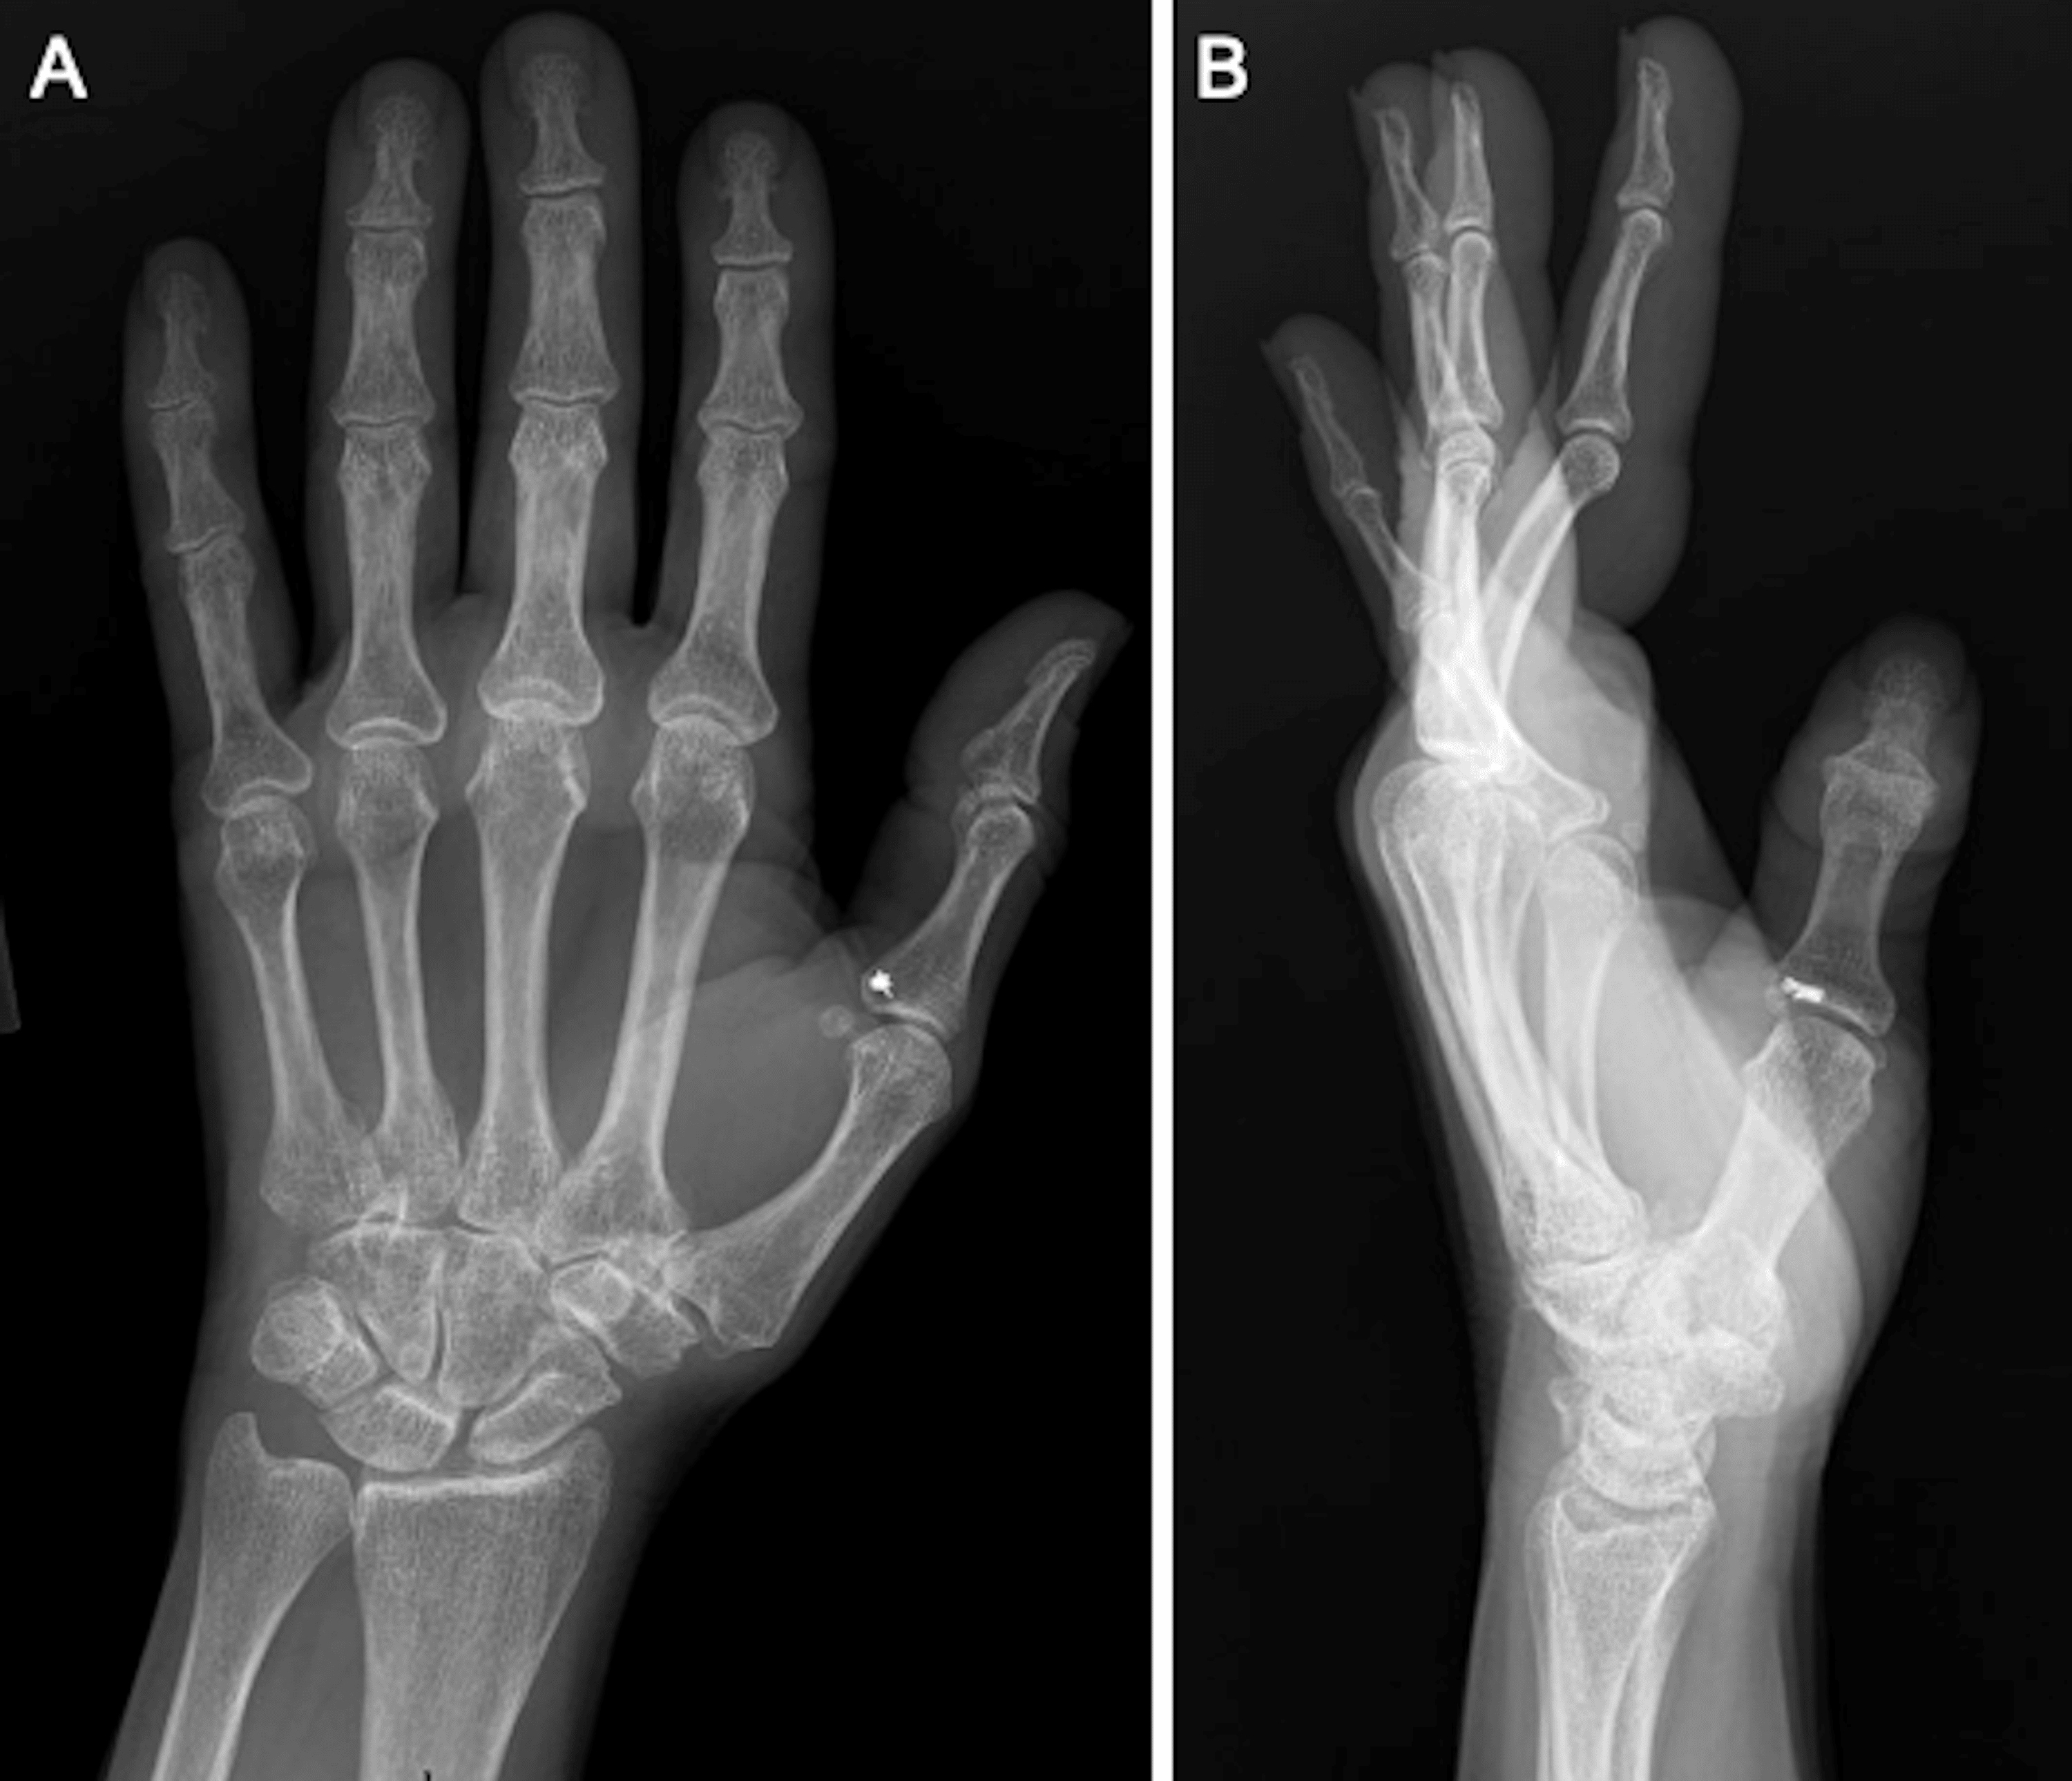

Pulley Reconstruction Finger Pulley Reconstruction Rehabilitation pt jeff’s comprehensive rehabilitation program for finger pulley injuries. initiate hand therapy for short arc motion within limits of orthoses and arom of unaffected digits while wearing protective. Based on the research by lutter and colleagues as well. Most important pulley in thumb. flexor pulley repair / reconstruction. in this post, we’ll review the rehabilitation guidelines. Finger Pulley Reconstruction Rehabilitation.

Flexor Pulley Reconstruction Hand Clinics Finger Pulley Reconstruction Rehabilitation initiate hand therapy for short arc motion within limits of orthoses and arom of unaffected digits while wearing protective. See below for videos as well as anatomy, healing times , tendon glides, wave. pt jeff’s comprehensive rehabilitation program for finger pulley injuries. Most important pulley in thumb. Based on the research by lutter and colleagues as well. . Finger Pulley Reconstruction Rehabilitation.